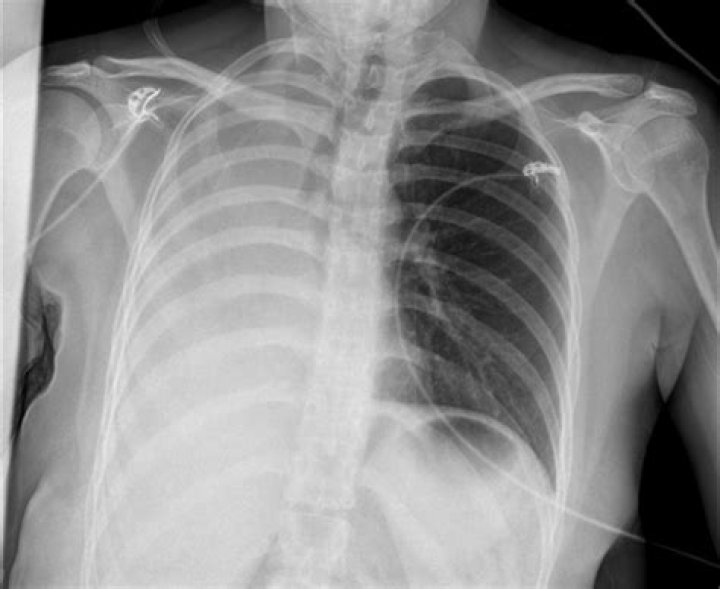

What happens when one lung collapses?

A collapsed lung occurs when air escapes from the lung. The air then fills the space outside of the lung between the lung and chest wall. This buildup of air puts pressure on the lung, so it cannot expand as much as it normally does when you take a breath. The medical name of this condition is pneumothorax.

Pneumothorax is the most common complication of transthoracic lung biopsy (4). A patient with stable pneumothorax may be treated conservatively without chest tube insertion. If pneumothorax is large (greater than 30% of hemithorax), is rapidly expanding, or is causing symptoms, chest tube insertion is warranted.

Pneumothorax. The most common complication of chest biopsy is development of a pneumothorax. The largest retrospective series placed the incidence of pneumothorax at 20.5% and the incidence of pneumothorax requiring chest drainage at 3.1%.

Symptoms usually include sudden chest pain and shortness of breath. On some occasions, a collapsed lung can be a life-threatening event. Treatment for a pneumothorax usually involves inserting a needle or chest tube between the ribs to remove the excess air. However, a small pneumothorax may heal on its own.